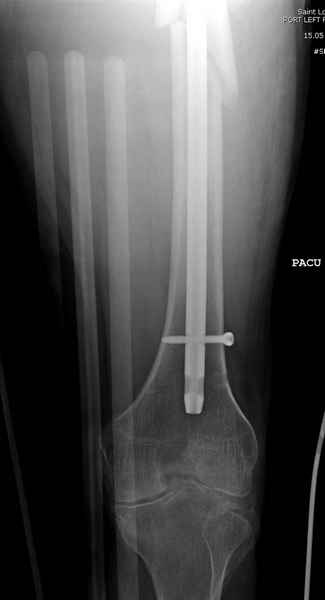

Учитывая, что случай ургентный, больной поступил вечером, не стали делать вытяжение и срочно провели операцию по фиксации перелома бедра антеградным штифтом Versa Nail от DePuy.

Для профилактики дальнейшего раскола в шейке предварительно во время проксимального рассверливания спереди и сзади провели временные спицы, которые в дальнейшем были заменены на шурупы (miss nail method)